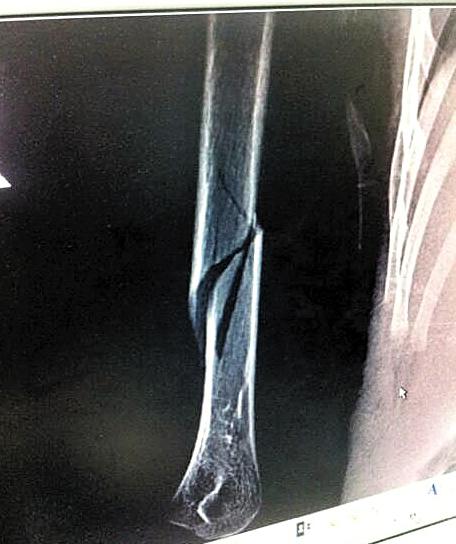

男童骨折照片

4岁的小劲右手打着石膏和夹板,他是位于广州市萝岗区的南方中英文学校小(2)班的学生,但已经一个月没有上幼儿园了。原因是7月14日,他的右手上臂被老师弄伤,导致骨折。在广州市正骨医院提供的放射检查报告单上,可以看见小劲右手上臂骨头中间有一处明显断裂。